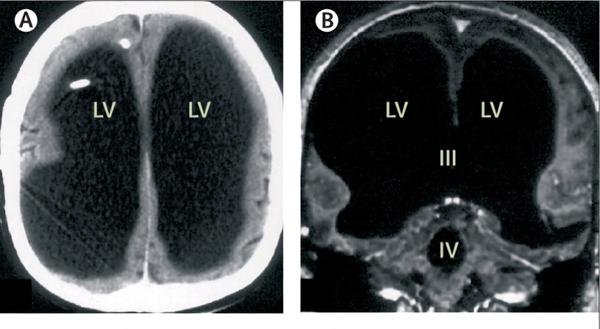

U Francuskoj je 2007. godine otkriven 44-godišnji čovjek kojem nedostaje čak 90% mozga a ima emocije ko i drugi, radi, ima dvoje djece i svjesnost o sebi. To iz korijena mijenja naša znanja o ljudskoj svijesti!

Senzacionalno otkriće vezano uz slučaj spomenutog Francuza koje je objavio i ugledni medicinski časopis „Lancet“ pokrenuo je i neke kognitivne psihologe poput Axela Cleeremansa koji je na jednom skupu u Buenos Airesu konstatirao da „mozak ima neshvatljive mogućnosti adaptacije i da 10% tkiva može zamijeniti cijelu strukturu“. Ta sposobnost poznata kao neuroplastičnost je ovdje ipak ekstremna jer je zamijenila ama baš sve strukture bez kojih ne možemo živjeti ni sekunde. Ukratko, ovaj čovjek ne bi smio biti živ ni u kom slučaju i njegova priča nadmašuje sva zabilježena čuda u našoj povijesti!

Slika: CT snimka mozga spomenutog Francuza na kojoj se jasno vidi da je cijela unutrašnjost lubanje ispunjena tekućinom a tek tanki sloj moždanog tkiva s unutarnje strane kostiju predstavlja mozak što čini samo 10% volumena normalnog ljudskog mozga! Uz sve to čovjek normalno funkcionira.